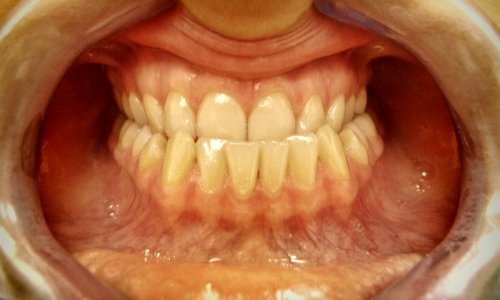

Idealny Zgryz

Rezultat: Leczenie zespołowe dało pozytywny efekt zarówno w odniesieniu do zgryzu, jak i do profilu twarzy.